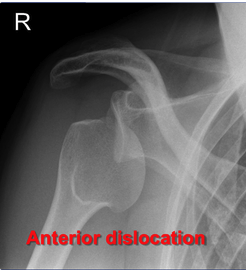

What is shown on this X-ray?